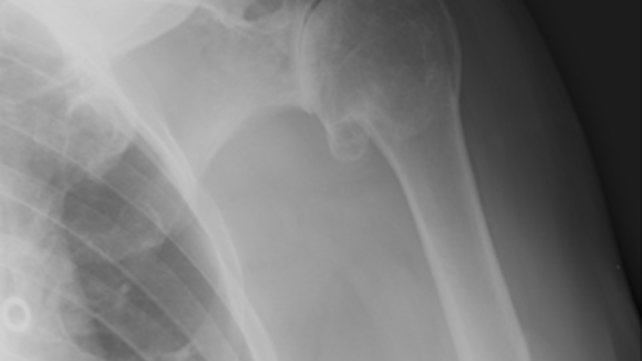

The COBRE for Skeletal Health and Repair at Rhode Island Hospital enables clinicians, scientists, engineers and biologists to work side by side on multidisciplinary research, helping to better understand cartilage and joint health mechanisms and develop strategies for the prevention and treatment of skeletal joint diseases.

The Center of Biomedical Research Excellence (COBRE) in Skeletal Health and Repair is working to learn more about joint disease.

There are currently more than 80 COBRE research centers in the US, and Rhode Island Hospital’s COBRE is one of just two that are nationally focused on bone and joint diseases.

The Rhode Island Hospital COBRE has the unique distinction of conducting research projects on both adult and pediatric skeletal health and diseases; conducting basic research as well as clinical and translational research; and working toward developing repair and regeneration strategies using tissue engineering.